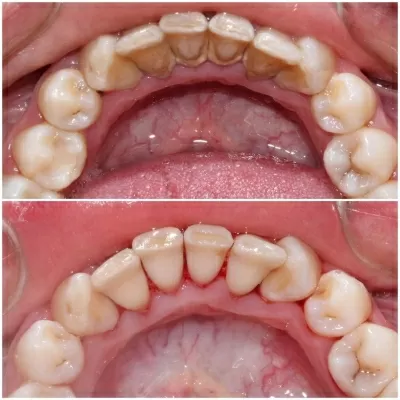

Хочу поблагодарить коллектив стоматологической клиники маэстро!!!Доктора Бардакова Игоря Викторовича и его замечательную команду, за высокий профессионализм чуткость и понимание к своим клиентам!!! Спасибо большое мои дорогие!!! Рекомендую всем кому не безразлична своя улыбка!! Приходите смело в клинику МАЭСТРО не ошибётесь!!!С Уважением Шахова раиса павловна

В стоматологическую клинику МАЭСТРО я пришла по рекомендации.Встретили меня очень тепло.ДОКТОР Игорь Викторович профессионал и умница. Зубы мои стали красивые, а я счастливая.Коллектив у Игоря Викторовича достойный.Как семья.Так приятно.СПАСИБО всему коллективу! Здоровья вам счастья,удачи,мира! Рекомендую всем, кому не все равно как выглядит ваша улыбка и здоровье ваших зубов читать далее